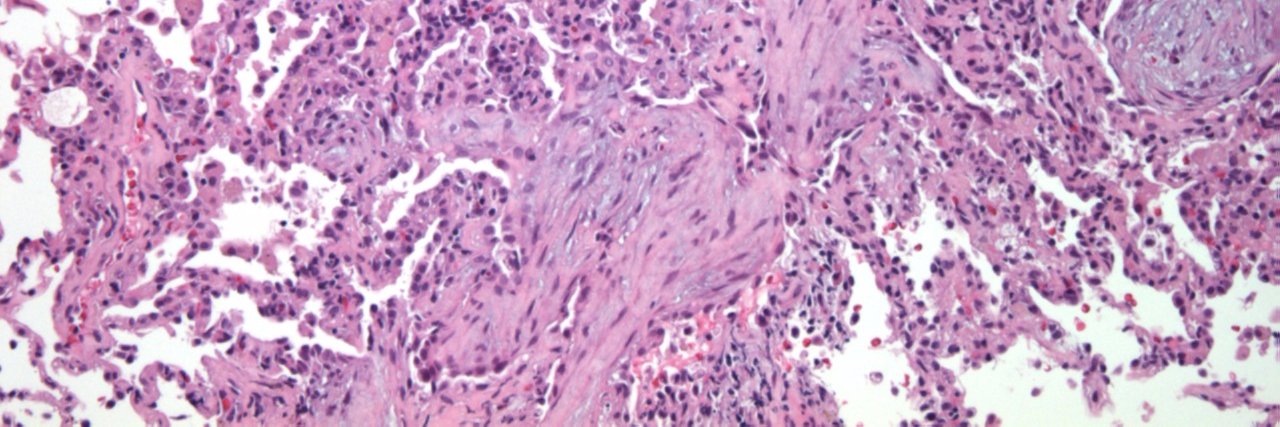

March's #PathArt winner (as voted by the CAP’s Digital Content Committee) is Junior Member Casey Schukow, DO. Check out Dr. Schukow’s piece, titled “Retina.” CAP members, submit your PathArt for next month's contest here: …ricanpathologists-bnaxn.formstack.com/forms/pathart_…